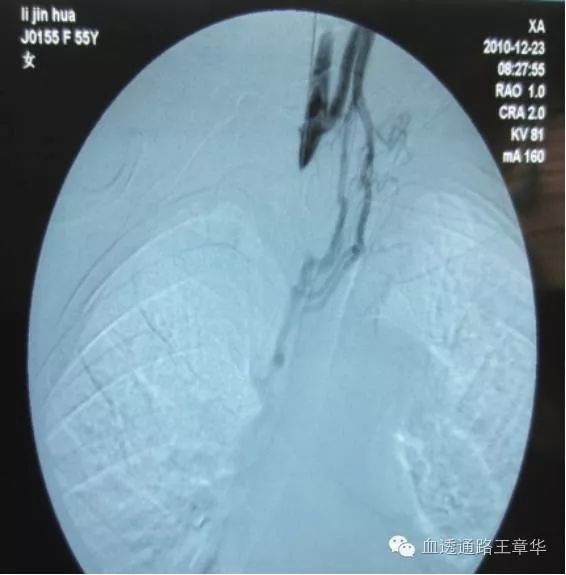

图示:肱动脉-贵要静脉侧侧吻合内瘘血流方向

及禁忌穿刺区域示意图